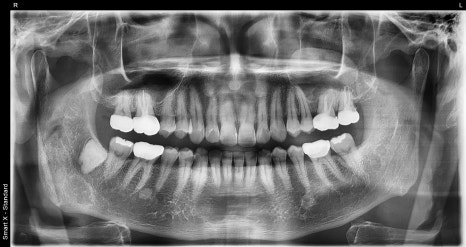

50대 남성 턱관절 환자의 초진 엑스레이 사진입니다.

파노라마와 관절 전용 촬영을 통해 양측 턱관절 디스크의 위치 이상(비대칭)과 관절 공간 협소 소견이 확인되었습니다.

50대 남성 환자분은“턱에서 딱 소리가 나고, 씹을 때마다 턱이 지그재그로 닫힌다”는 증상으로 내원하셨습니다.

초진 시

정밀 파노라마 촬영과 청진기 청진,

해부학 기반 진단을 통해 턱관절 디스크 장애로 진단되었고

약 한 달간 약물치료(근육이완제)와 PHL-15 기계로 물리치료를 병행하였습니다.